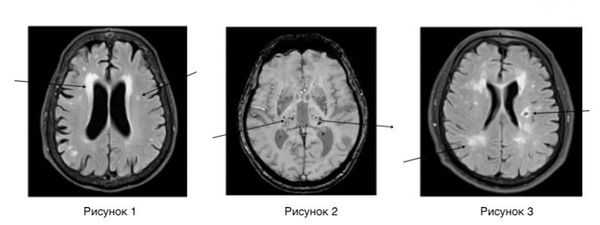

Нейровизуализационные методы: КТ, МРТ головного мозга, МР-ангиография (артерии и вены головного мозга ), при необходимости рентгеноконтрастная церебральная ангиография. Нейровизуализация позволяет исключить другие заболевания (опухоль, гидроцефалию) и подтвердить сосудистый характер нарушений. Предпочтительнее МРТ головного мозга, на которой выявляются характерные для хронической ишемии мозга изменения:

- лейкоареоз — изменение белого вещества вокруг желудочков головного мозга (на рисунке 1, белое свечение вокруг желудочков);

- лекоэнцефалопатия — поражение белого вещества головного мозга (на рисунке 1 и 3, светлые участки в подкорковом веществе);

- малые инфаркты, ишемические инсульты (рисунок 3);

- множественные микрокровоизлияния (рисунок 2 — темные участки);

- атрофия коры головного мозга.

Существует зависимость между типом и выраженностью морфологических изменений мозгового вещества и стадией заболевания [4] [6] .